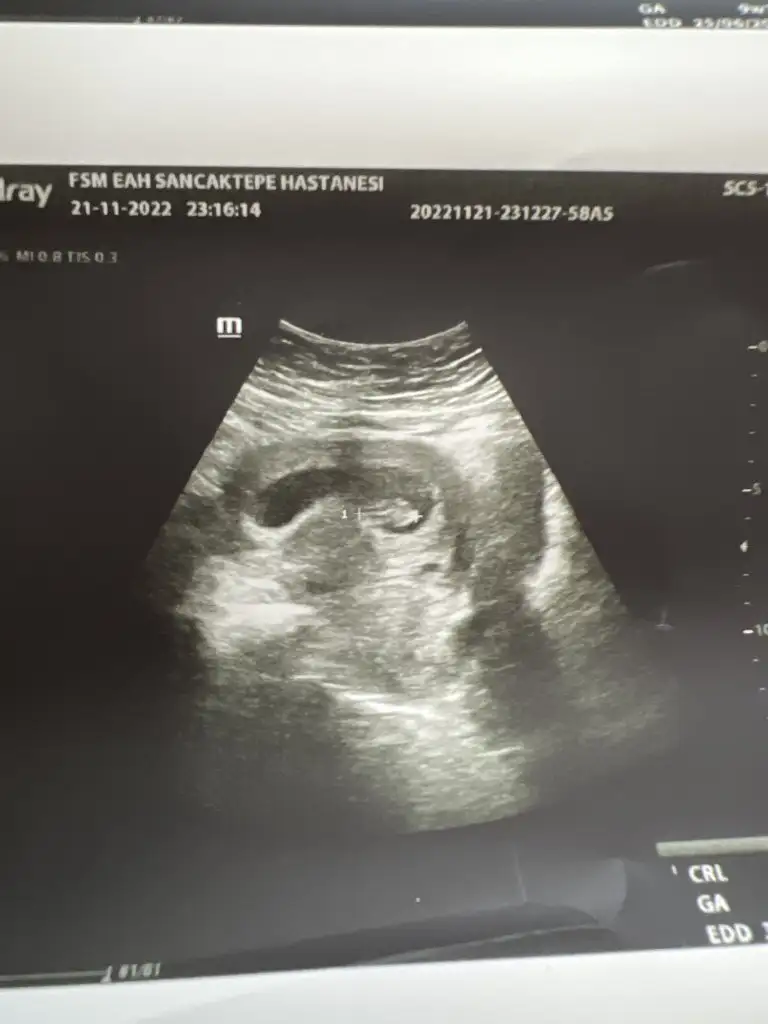

Merhaba banada tahmin yaparmısınızSelam Kızlarbir çok kişi gruplardan beni bilir. Yine yetiştim imdatlara

Çoook uzun bir süre araştırma okuma yaptıktan sonra sizlere bu başlığı açtım çevremde tüm gebelere de denedim. Bunun sırrını çözen İnstagramda (isim vermeyim) işi ticarete dökmüş bile.Nub, Ramzi,Çin Rus Japon Takvimleri, Yüzük Yöntemi bir çok şey size sayabilirim.

5 ve 14. haftaya kadar olan ultrason fotolarınızı paylaşın. Vajinadan mı yoksa karından mı çekildiğini ve kaç haftalık olduğunu da mutlaka belirtin.

Not: Tahmin yaptığım anneler cinsiyet öğrendikten sonra lütfen bana geri dönüş yapın

Benim daha bebem gözükmüyo kesem gözüküyo olur mu

Önümüzdeki hafta inşallah göreceğim doktor daha nokta kadar dedi bebeme daha çok minnakmışşKesenin şekline göre yorum yapanlar var. Gözükecek inşallah sabır